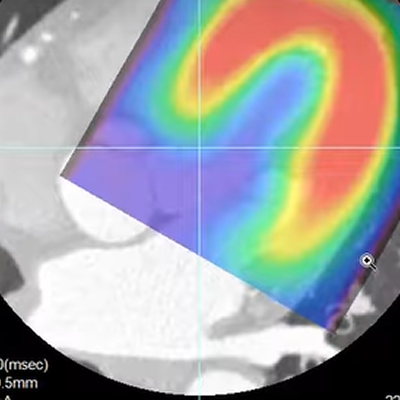

This protocol fuses functional (SPECT) and anatomic (CT) cardiac studies, supporting analysis of stress, rest and reversibility.